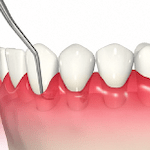

・歯周ポケット掻爬

痛みが出ないよう麻酔を行い、歯周ポケットのより深いところに付着した歯石や汚れをスケーリングやルートプレーニング同様の器具で掻き出し除去します。

・歯肉剥離掻爬術(フラップ法、Fop)

歯周ポケットが深く、器具が歯石や汚れに届かない場合や除去しきれない場合に、歯茎を切開して目視下で直接的に除去します。